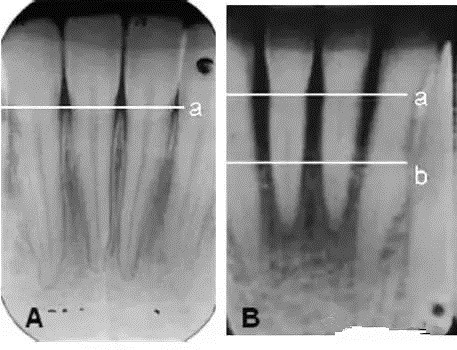

下頜前牙的X光片。圖A和B中的a線所示是正常的牙槽骨高度,圖B中的b線所示為(wei) 牙周炎導致的牙槽骨吸收後的高度,隻為(wei) 正常高度的1/2。牙周炎不僅(jin) 會(hui) 導致牙齒鬆動脫落,更可能影響全身健康,比如加重心腦血管疾病、糖尿病、影響呼吸與(yu) 消化係統。